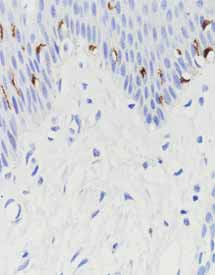

产品名称:Langerin

产品编号:MAB-1068

阳性部位:细胞膜/细胞质

图片描述:

皮肤,langerin染色,细胞膜/细胞质阳性